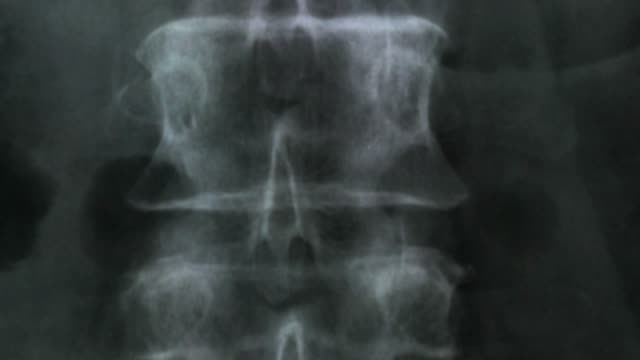

척추협착증은 신체의 허리 부분에 협착이 생기는 질환으로, 허리 디스크가 압박을 받아 디스크의 내부 물질이 신경에 압박을 주게 됩니다.

척추관협착증은 척추 주변의 근육과 인대가 퇴행하여 척추관 내 황색 인대가 비정상적으로 부풀어 오르면서 발생하는 퇴행성 척추질환 중 하나입니다. 이 질환은 가까운 거리도 통증으로 인해 걷기가 어려워지는 특징을 가지고 있으며, 새벽에 다리에 통증을 느끼는 경우가 많습니다.

척추관협착증은 다른 척추 질환에 비해 퇴계 정도가 매우 심한 질환으로, 퇴행이 심할수록 근육과 인대가 더욱 뭉쳐지고 더 많은 압력을 가하게 됩니다. 이 때문에 근육과 인대를 풀어주는 것이 중요하며, 이를 위한 가장 적합한 운동이 걷기입니다.